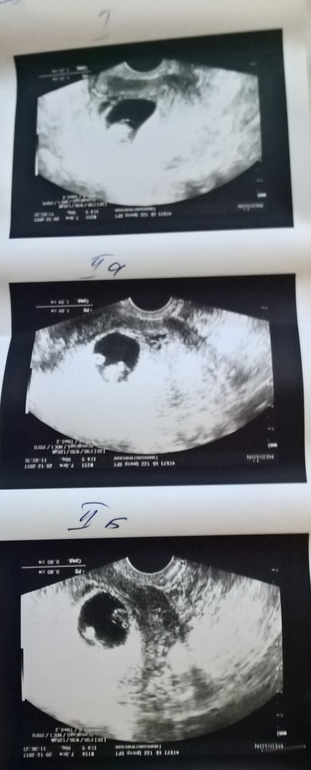

Второе УЗИ

Сходила на второе узи,у двух плодов сб плюс.У третьего нет,похоже замер.